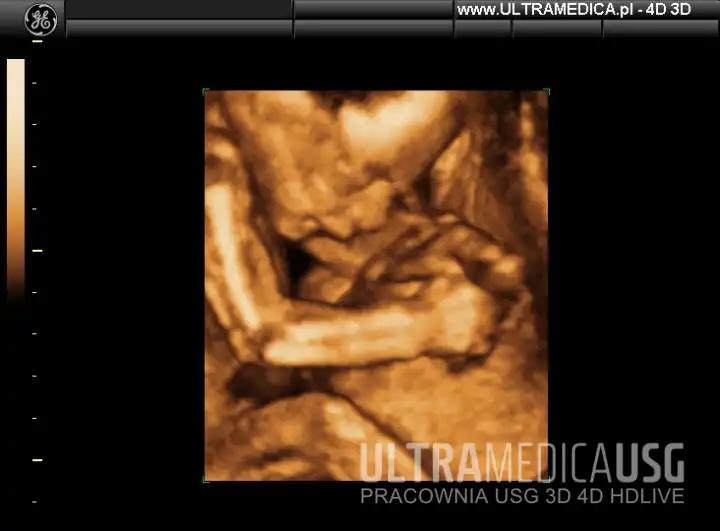

USG połówkowe może brzmieć jak skomplikowane hasło superbohatera, jednak w rzeczywistości stanowi jedno z najistotniejszych badań w czasie ciąży. Wykonuje się je między 18. a 22. tygodniem, kiedy lekarz ocenia rozwijającego się malucha. Dlaczego akurat w tym okresie? Otóż w tym czasie dziecko ma już swoje małe organy, co pozwala specjaliście dokładnie przyjrzeć się wszystkiemu, co zachodzi w brzuszku, począwszy od główki aż po stópki. To właśnie wtedy płód zaczyna orientować się w przestrzeni, co znacząco ułatwia pracę lekarza!

Podczas badania lekarz szczegółowo ocenia anatomię dziecka. Tutaj nie ma miejsca na oszustwa, a średnia waga płodu to nie żadna bajka. Rzeczywisty przegląd obejmuje pomiar obwodu główki, długości kości oraz sprawdzanie stanu kręgosłupa, ponieważ wszelkie wady mogą prowadzić do licznych problemów. Oczywiście lekarz również kontroluje stan narządu rodnego, a rodzice często na tym etapie odkrywają, czy szykują się na kolejne różowe lub niebieskie zakupy. Warto jednak pamiętać, że lekarz nie daje 100% pewności, choć USG połówkowe potrafi wykryć około 90% wad wrodzonych!

Pamiętaj, że USG połówkowe to znacznie więcej niż tylko sprawdzenie, czy maluszek ma wszystkie paluszki (co z pewnością jest ważne!). To także doskonała okazja do odkrycia ewentualnych wad wrodzonych. Podczas badań lekarz sprawdza każdy element, począwszy od głowy, przez brzuch, aż po kończyny. To, co może ujrzeć na ekranie, naprawdę fascynuje! Kobiety siedzące na krawędzi fotela będą miały szansę zobaczyć, czy ich dziecko ma prawidłowo uformowane serce, czy nie cierpi na wodogłowie, a nawet jakie ma rysy twarzy! Niezłe, prawda? Poza tym USG połówkowe umożliwia także określenie płci, więc już wkrótce możecie zmienić kolor wyprawki na odpowiedni!

W trakcie USG połówkowego lekarz stanie się archeologiem, odkrywającym tajemnice Twojego dziecka. Zajmie się różnymi pomiarami, takimi jak obwód głowy, długość kości udowej i wiele innych. To pełnowymiarowy przegląd, który pokaże, czy maluszek rozwija się zgodnie z planem. Jeżeli masz ochotę poznać płeć, nie wahaj się domagać od lekarza gorliwego zajęcia się także „sprawami płciowymi” – w końcu każdy rodzic pragnie wiedzieć, czy w przyszłości czeka go męski lub żeński „kolorowy” remont w pokoju!